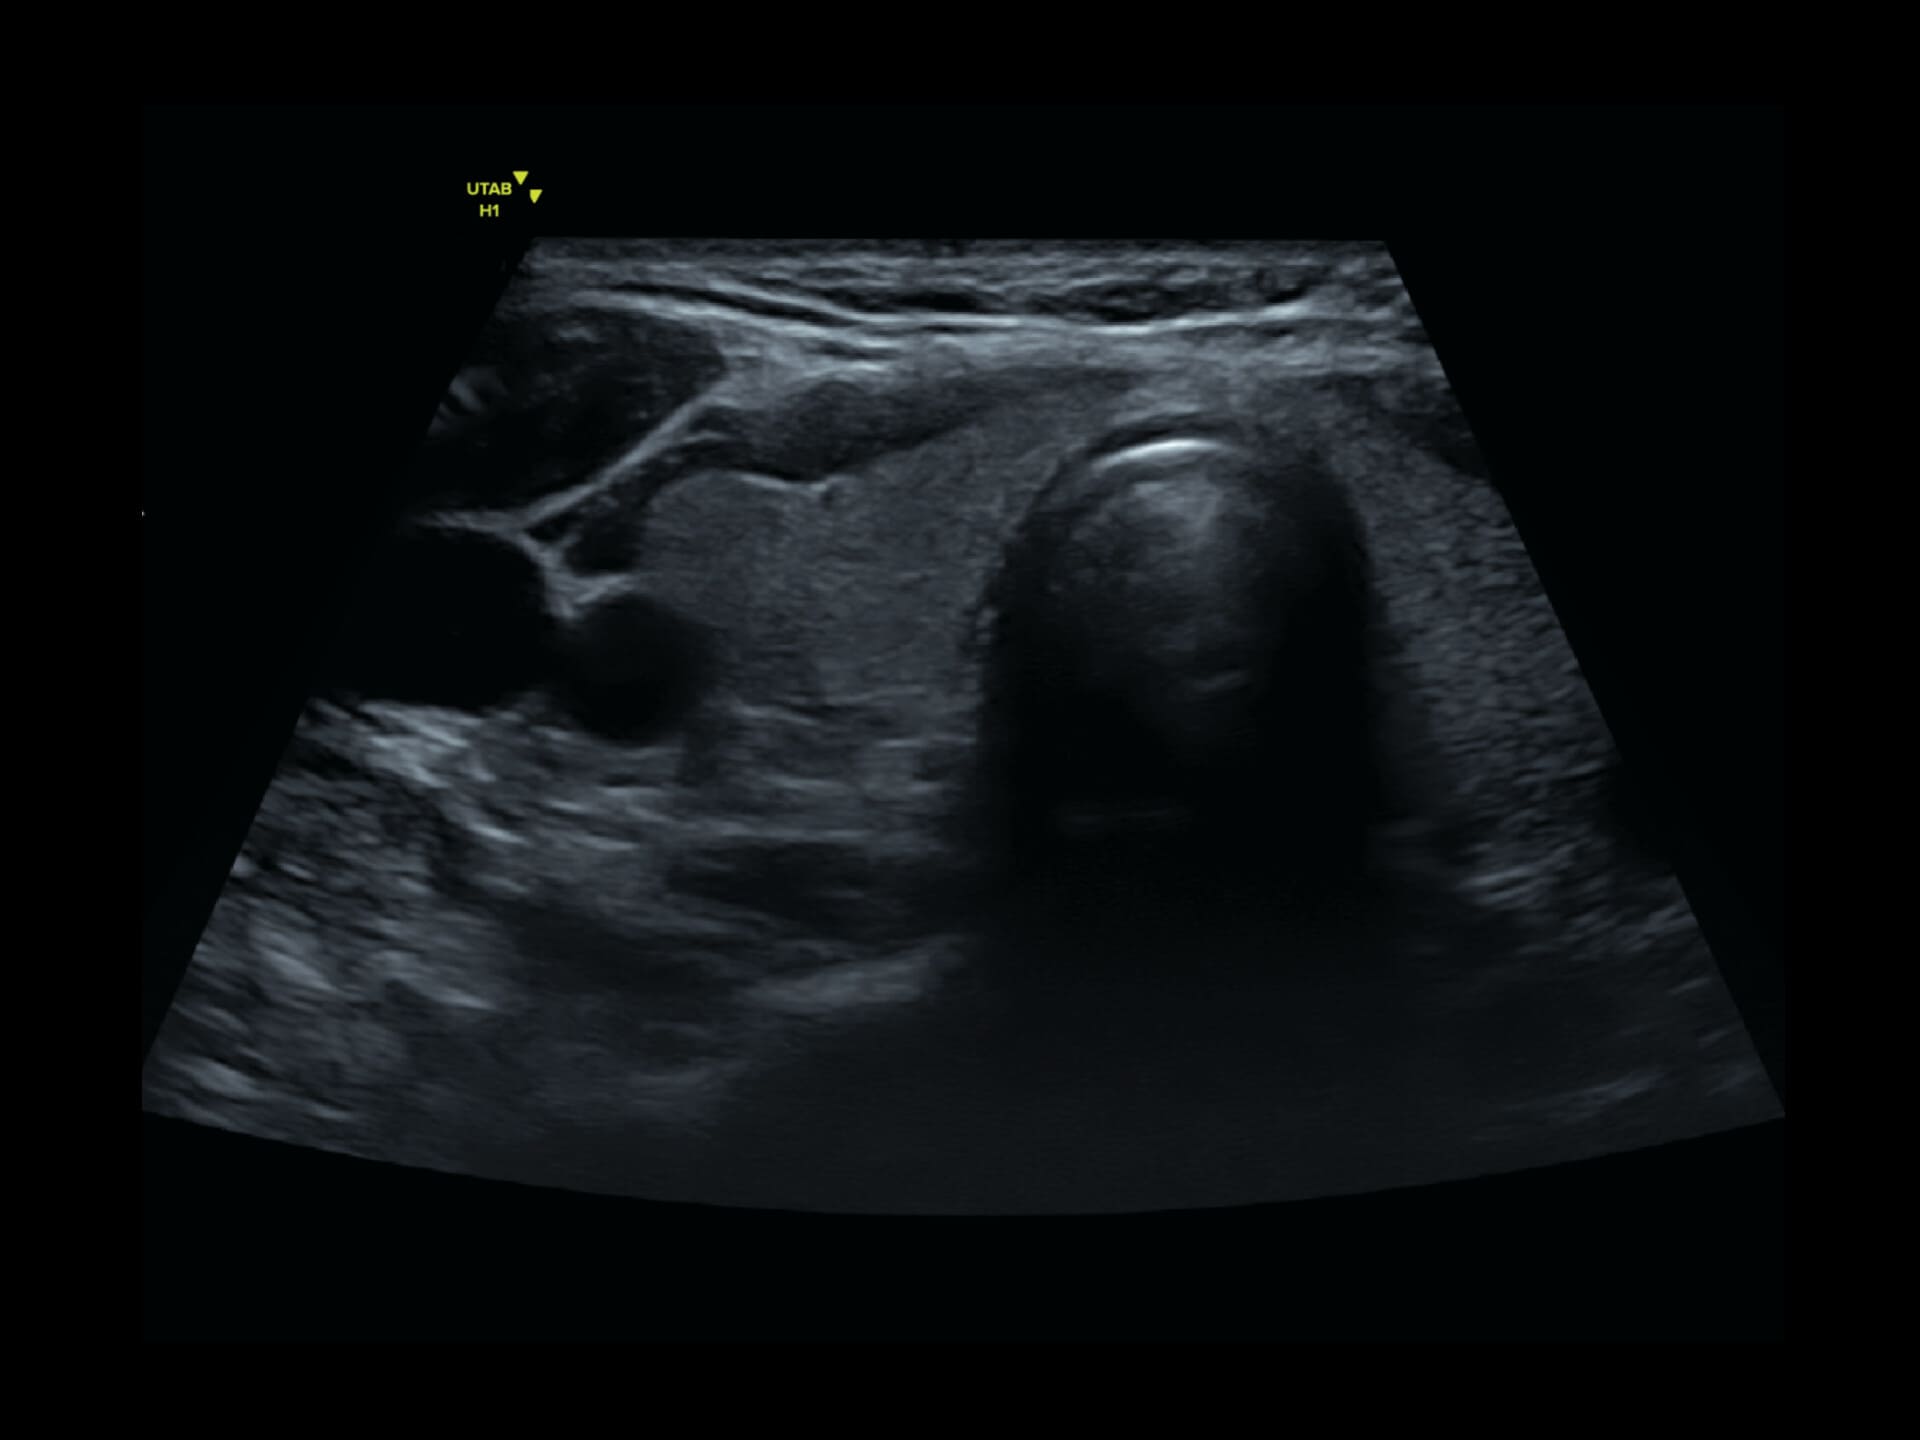

L9-2 Linear Array Probe

Precision at the Surface

Crystal-clear imaging for muscles, vessels, and soft tissues—perfect for targeted exams and real-time procedures.

The L9 – 2 is a linear array ultrasound probe featuring advanced wideband technology, which enables a broader frequency range for superior image resolution and clarity. This enhanced imaging capability makes it ideal for a range of clinical applications.

About L9-2

The L9 – 2 is a linear array ultrasound probe featuring advanced wideband technology, which enables a broader frequency range for superior image resolution and clarity.

This enhanced imaging capability makes it ideal for a range of clinical applications.

L9 - 2 Linear Array Probe

2 - 10 MHz

DLP

192 elements

Applications:

Musculoskeletal, Thyroid, Small Parts, Pediatrics, Peripheral Vascular, Breast, Obstetrics

B-mode, HI, XBeam, Speckle Reduction, Virtual Convex, M-mode, PW (Update, Duplex, Triplex, HPRF), CFM, PD

7 x 43 mm